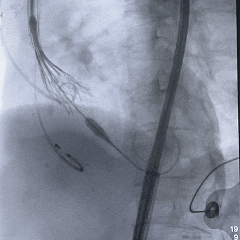

工作位造影:无冠窦侧瓣下2mm左右,瓣膜形态直筒

左冠切线位,可见左冠开口无遮挡

多角度观察,确认瓣膜稳定

脱钩后造影,瓣膜位置可,几乎无瓣周漏

左冠切线造影,确认冠脉无遮挡

外周血管造影无损伤,手术结束